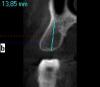

Wasja Опубликовано 29 декабря, 2012 Поделиться Опубликовано 29 декабря, 2012 С агрессивными вообще проблем нет.Диагностическая нарезка КТ. Ссылка на комментарий